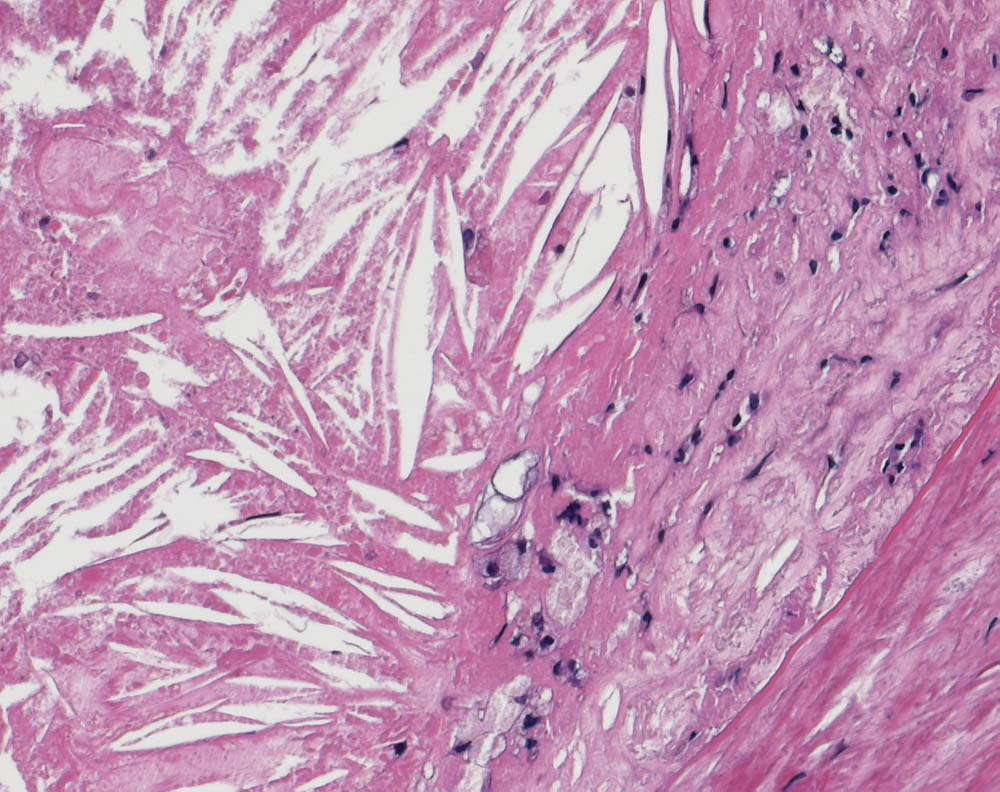

Bildausschnitt aus einem Atherom bestehend aus teils zerfallenen Schaumzellen und wetzsteinförmigen herausgelösten Cholesterinkristallen.

Die Cholesterinkristalle entstehen nach dem Zerfall von lipidbeladenen Makrophagen.